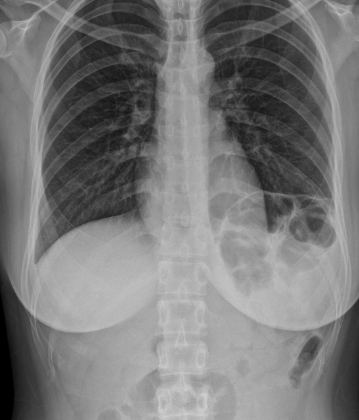

탈장이란 신체의 장기가 제자리에 있지 않고 다른 조직을 통해 돌출되거나 빠져나오는 증상을 말합니다. 신체 어느 곳에나 생길 수 있지만 대부분의 탈장은 복벽, 즉 배 안의 앞쪽의 벽에서 발생하는데, 복벽 탈장은 복강을 둘러싼 근육과 근막 사이에 복막이 주머니 모양으로 돌출되어 비정상적인 형태를 이루는 상태입니다. 주머니 속에 복강 내 장기가 포함되기도 한다. 탈장은 생긴 부위에 따라 여러 가지로 분류되기도 합니다.